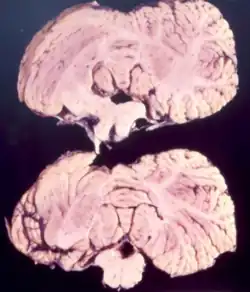

Neuropathology

Studies from kuru infected individuals have revealed information explaining the effects that the disease can have on the brain. In the early stages of the disease, infected individuals may experience withdrawal, incoordination, tremors, and curling of the toes and feet.[17] To understand these difficulties in balance and coordination, studies were conducted to analyze the brain of kuru infected individuals. These studies by Klatzo et al., found that neurons in a kuru infected brain were abnormally small and lighter in color compared to their healthy counterparts.[17] Affected neurons appear "moth-eaten" due to their characteristic deformations. [17] These abnormalities in the neurons of the brain infected by kuru were similar to those with Creutzfeldt-Jakob disease (CJD).[17]